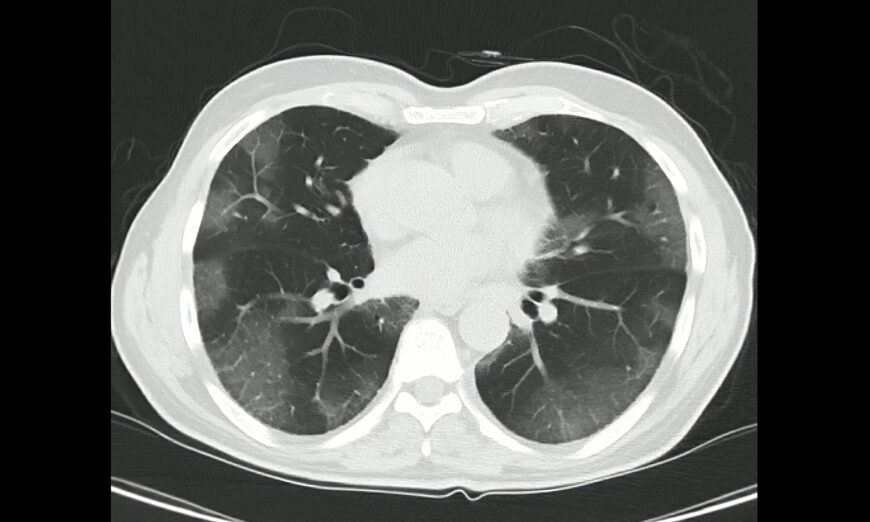

‘Điều này thật vô lý’: Các chuyên gia cố gắng giải thích tình trạng phổi trắng ở Trung Quốc

Trong khi dữ liệu chính thức từ Trung Quốc chỉ ghi nhận các ca bệnh nhẹ và tỷ lệ tử vong thấp xoay quanh đợt bùng phát COVID-19 mới đây nhất, thì mạng xã hội…

Những câu chuyện về tình trạng ‘phổi trắng’ tràn ngập mạng xã hội Trung Quốc

“Phổi trắng” đã trở thành thuật ngữ được tìm kiếm nhiều nhất trên mạng xã hội Trung Quốc trong bối cảnh dịch bệnh bùng phát khắp cả nước.